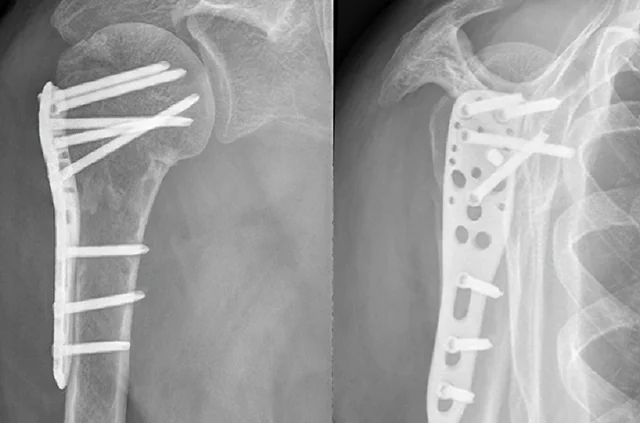

Operativno lečenje preloma ramena

Operativno lečenje ima za cilj da se polomljeni fragmenti dovedu u prvobitni položaj i stabilizuju. Uglavnom se primenjuje kod preloma gornjeg dela nadlaktice, pri čemu se stabilizacija najčešće sprovodi pločicom i šrafovima ili tzv. klinom. Ukoliko se, nakon što prelom sraste, ne dobije zadovoljavajući obim pokreta, preporučuje se vađenje pločice i tzv. release (popuštanje, oslobađanje od priraslica) ramena. Prelomi ramena, bez obzira na način tretiranja, često za posledicu imaju smanjenu pokretljivost ramena, a ponekad i bolove pri pokretima.

Osteosinteza preloma ramena, rendgenski snimak

Osteosinteza preloma ramena